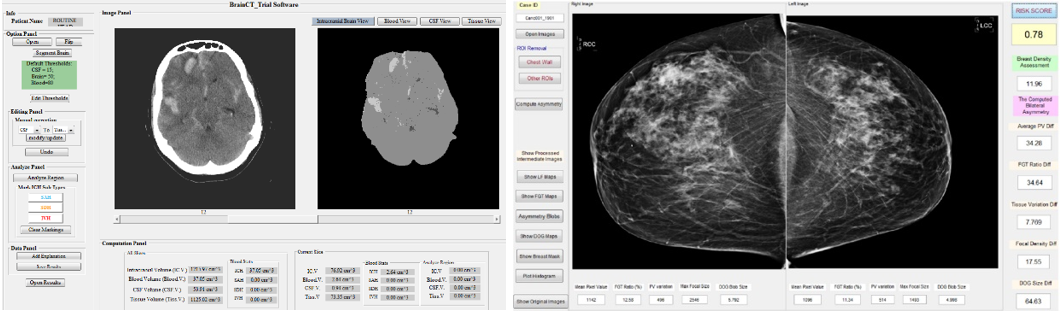

Images on the right show examples of CT images recently annotated by a radiologist to support medical imaging research to identify quantitative image markers to help diagnosis of pancreatic tumors. Based on RECIST guidelines, two maximum perpendicular diameters of the central tumor region are measured and marked (as shown in images). In these four images, two tumors (on the top) are verified pancreatic adenocarcinoma, while two tumors (on the bottom) are intraductal papillary mucinous neoplasm (left) and serous cystadenomas (right), which currently are benign, but have a risk of progressing to pancreatic cancer.